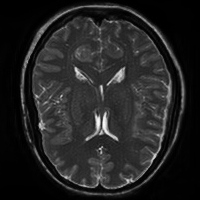

4.4 Qualitative Evaluation

In Figure 5 we analyze the prediction quality of our and compared approaches in a qualitative way. Considering modality propagation in MRI, we see that usage of uncertainty-aware patch invariance (UAPI) gives a better detailed weighting of the cerebrospinal fluid in the middle of the brain. In general, employing patch invariance yields better preservation of fine structures. This observation also applies to accelerated MRI enhancement. In particular, CUT and UAPI provide comparatively sharper knee images with more high-frequency details than the other methods.